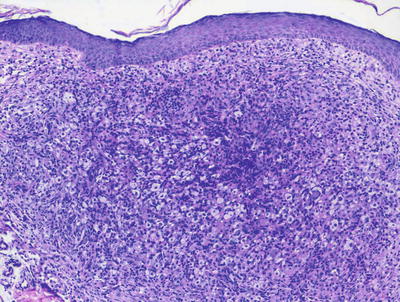

In LCH, the epidermis demonstrates focal parakeratosis overlying varying degrees of spongiosis that is diffuse throughout the epidermis. In most cases, there is abundant exocytosis of Langerhans cells into the epidermis (Fig. 22.3). Langerhans cells can usually be identified based upon cytologic features that include reniform-shaped, grooved, or folded nuclei and abundant cytoplasm (Figs. 22.4 and 22.5). Anti-CD1 a immunohistochemistry is useful in cases when the nature of the infiltrating cells is not readily apparent. Intraepidermal eosinophils are also quite common. Cytologic atypia and significant mitotic activity are rarely encountered. Some cases fail to demonstrate exocytosis of Langerhans cells into the dermis. Treatment with topical corticosteroids prior to biopsy may also suppress exocytosis and mask the diagnostic features.

Fig. 22.3

Marked epidermotropism of Langerhans cells into the epidermis is seen in most cases of Langerhans cell histiocytosis